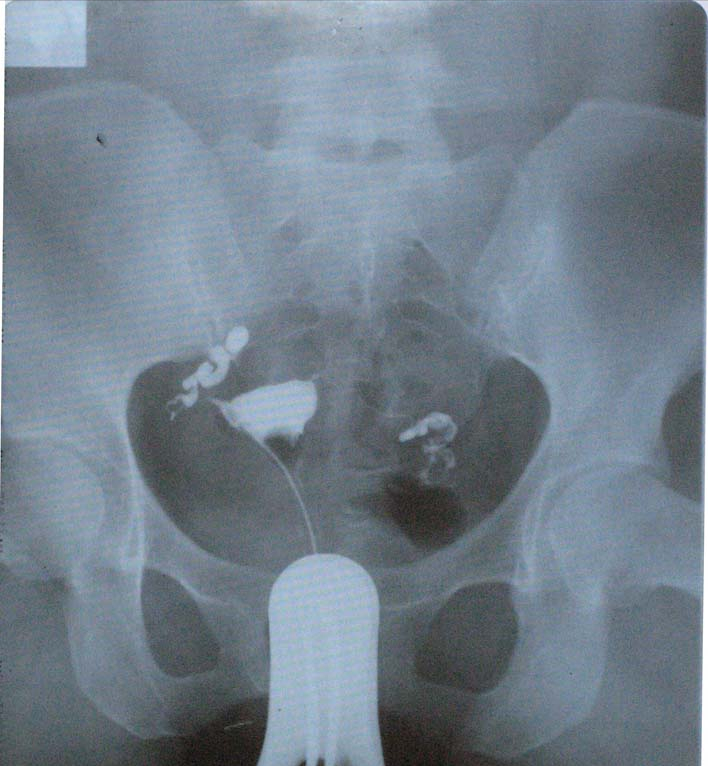

输卵管水肿,顾名思义就是输卵管阻塞后,它所产生的分泌物无法排出而累积在输管腔内,久而久之就造成了输卵管整条肿大(可以把它想像成一条香肠样)。

输卵管水肿手术治疗方式目前有两种。第一种是把水肿那侧整条输卵管以微创内视镜切除;另一种是把水肿那侧输卵管和子宫连接处用内视镜手术阻断/结扎。